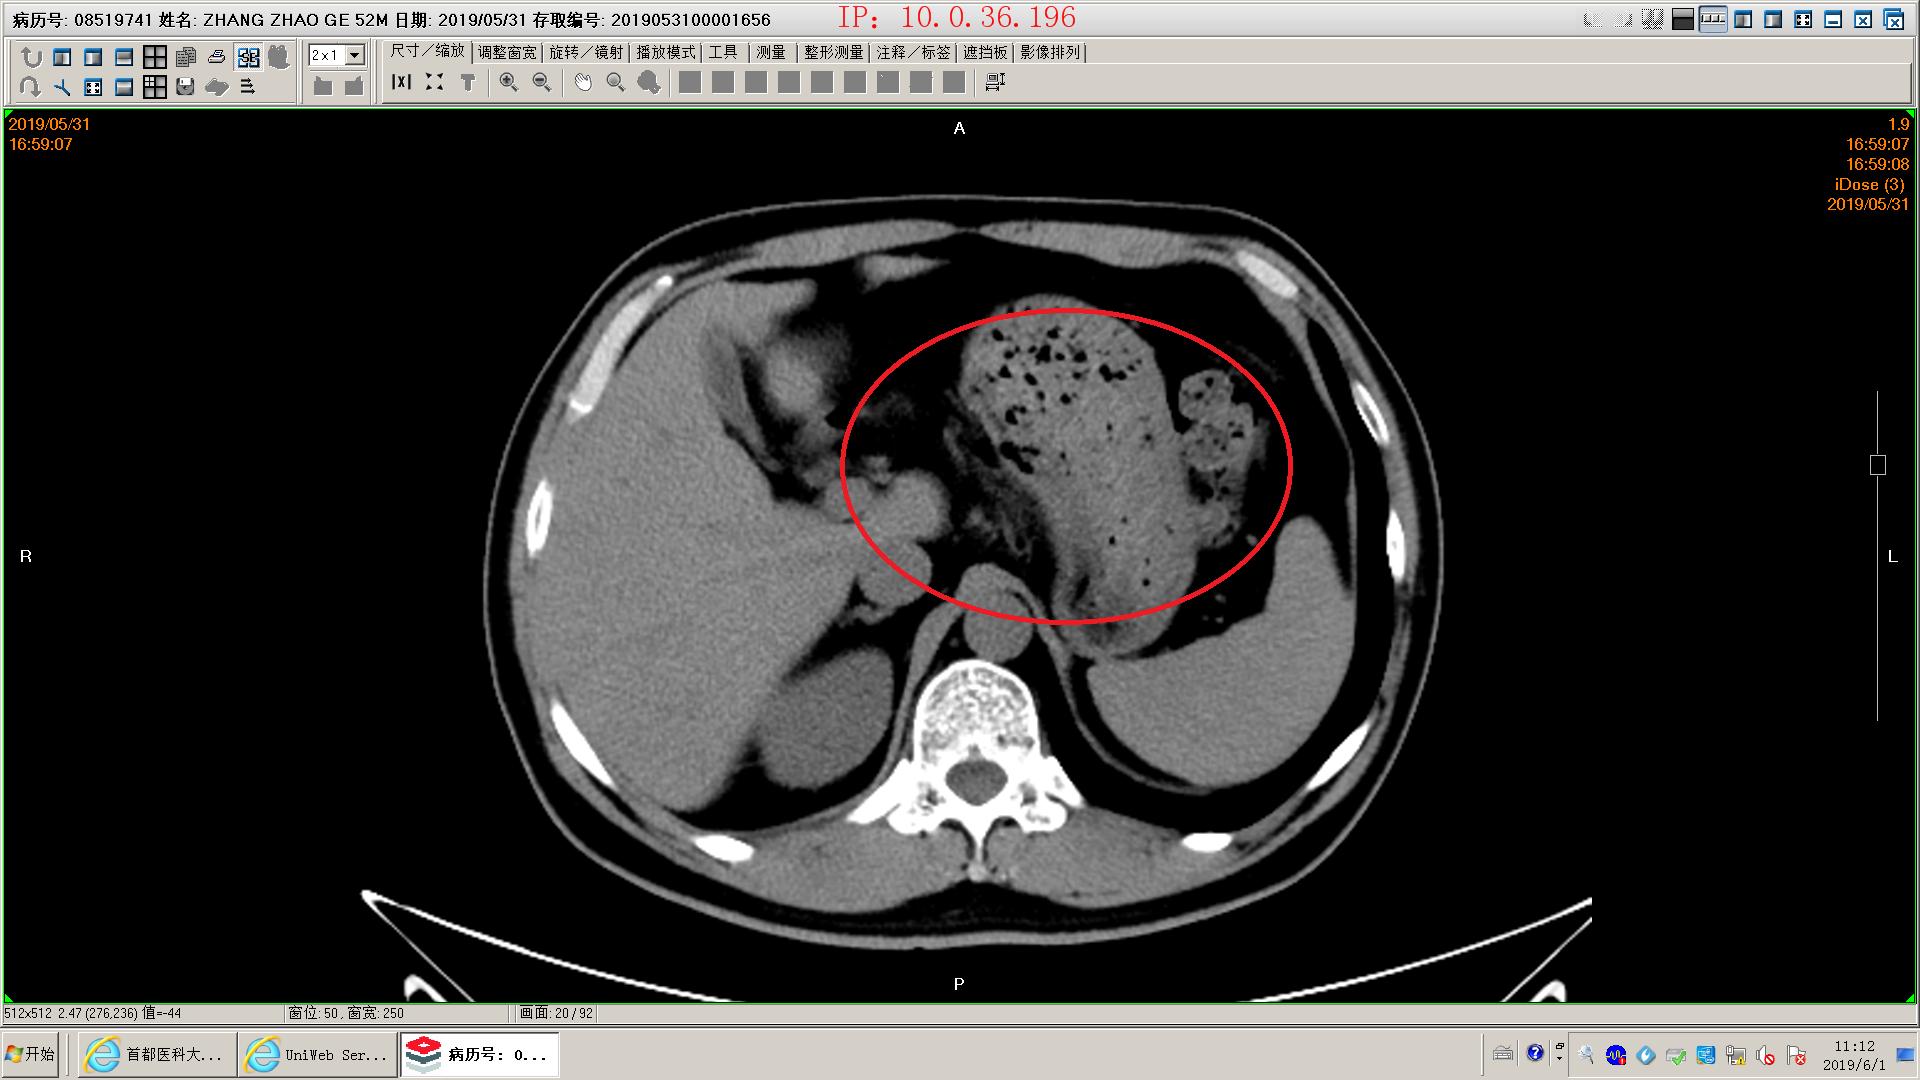

下面是一例胆源性胰腺炎影像学和化验表现,这个病人没有脏器功能不全,胰腺坏死不明显,周围没有明显积液,还不是重症胰腺炎。虽然有可疑胆管结石,但是没有黄疸,我们会在做核磁mrcp证实一下结石的位置。患者胃里面有一些残存的食物,我们会用胃管做胃肠减压,有助于胃肠道休息恢复;肠道里面积存的粪便也比较多,肠鸣音听不到,通过肥皂水灌肠促进肠道蠕动排除,有助于胃肠道功能恢复。然后给予生长抑素抑制胰酶分泌,禁食水补液,消炎治疗。

胰腺模糊渗出,坏死不明显

胰腺间隙模糊